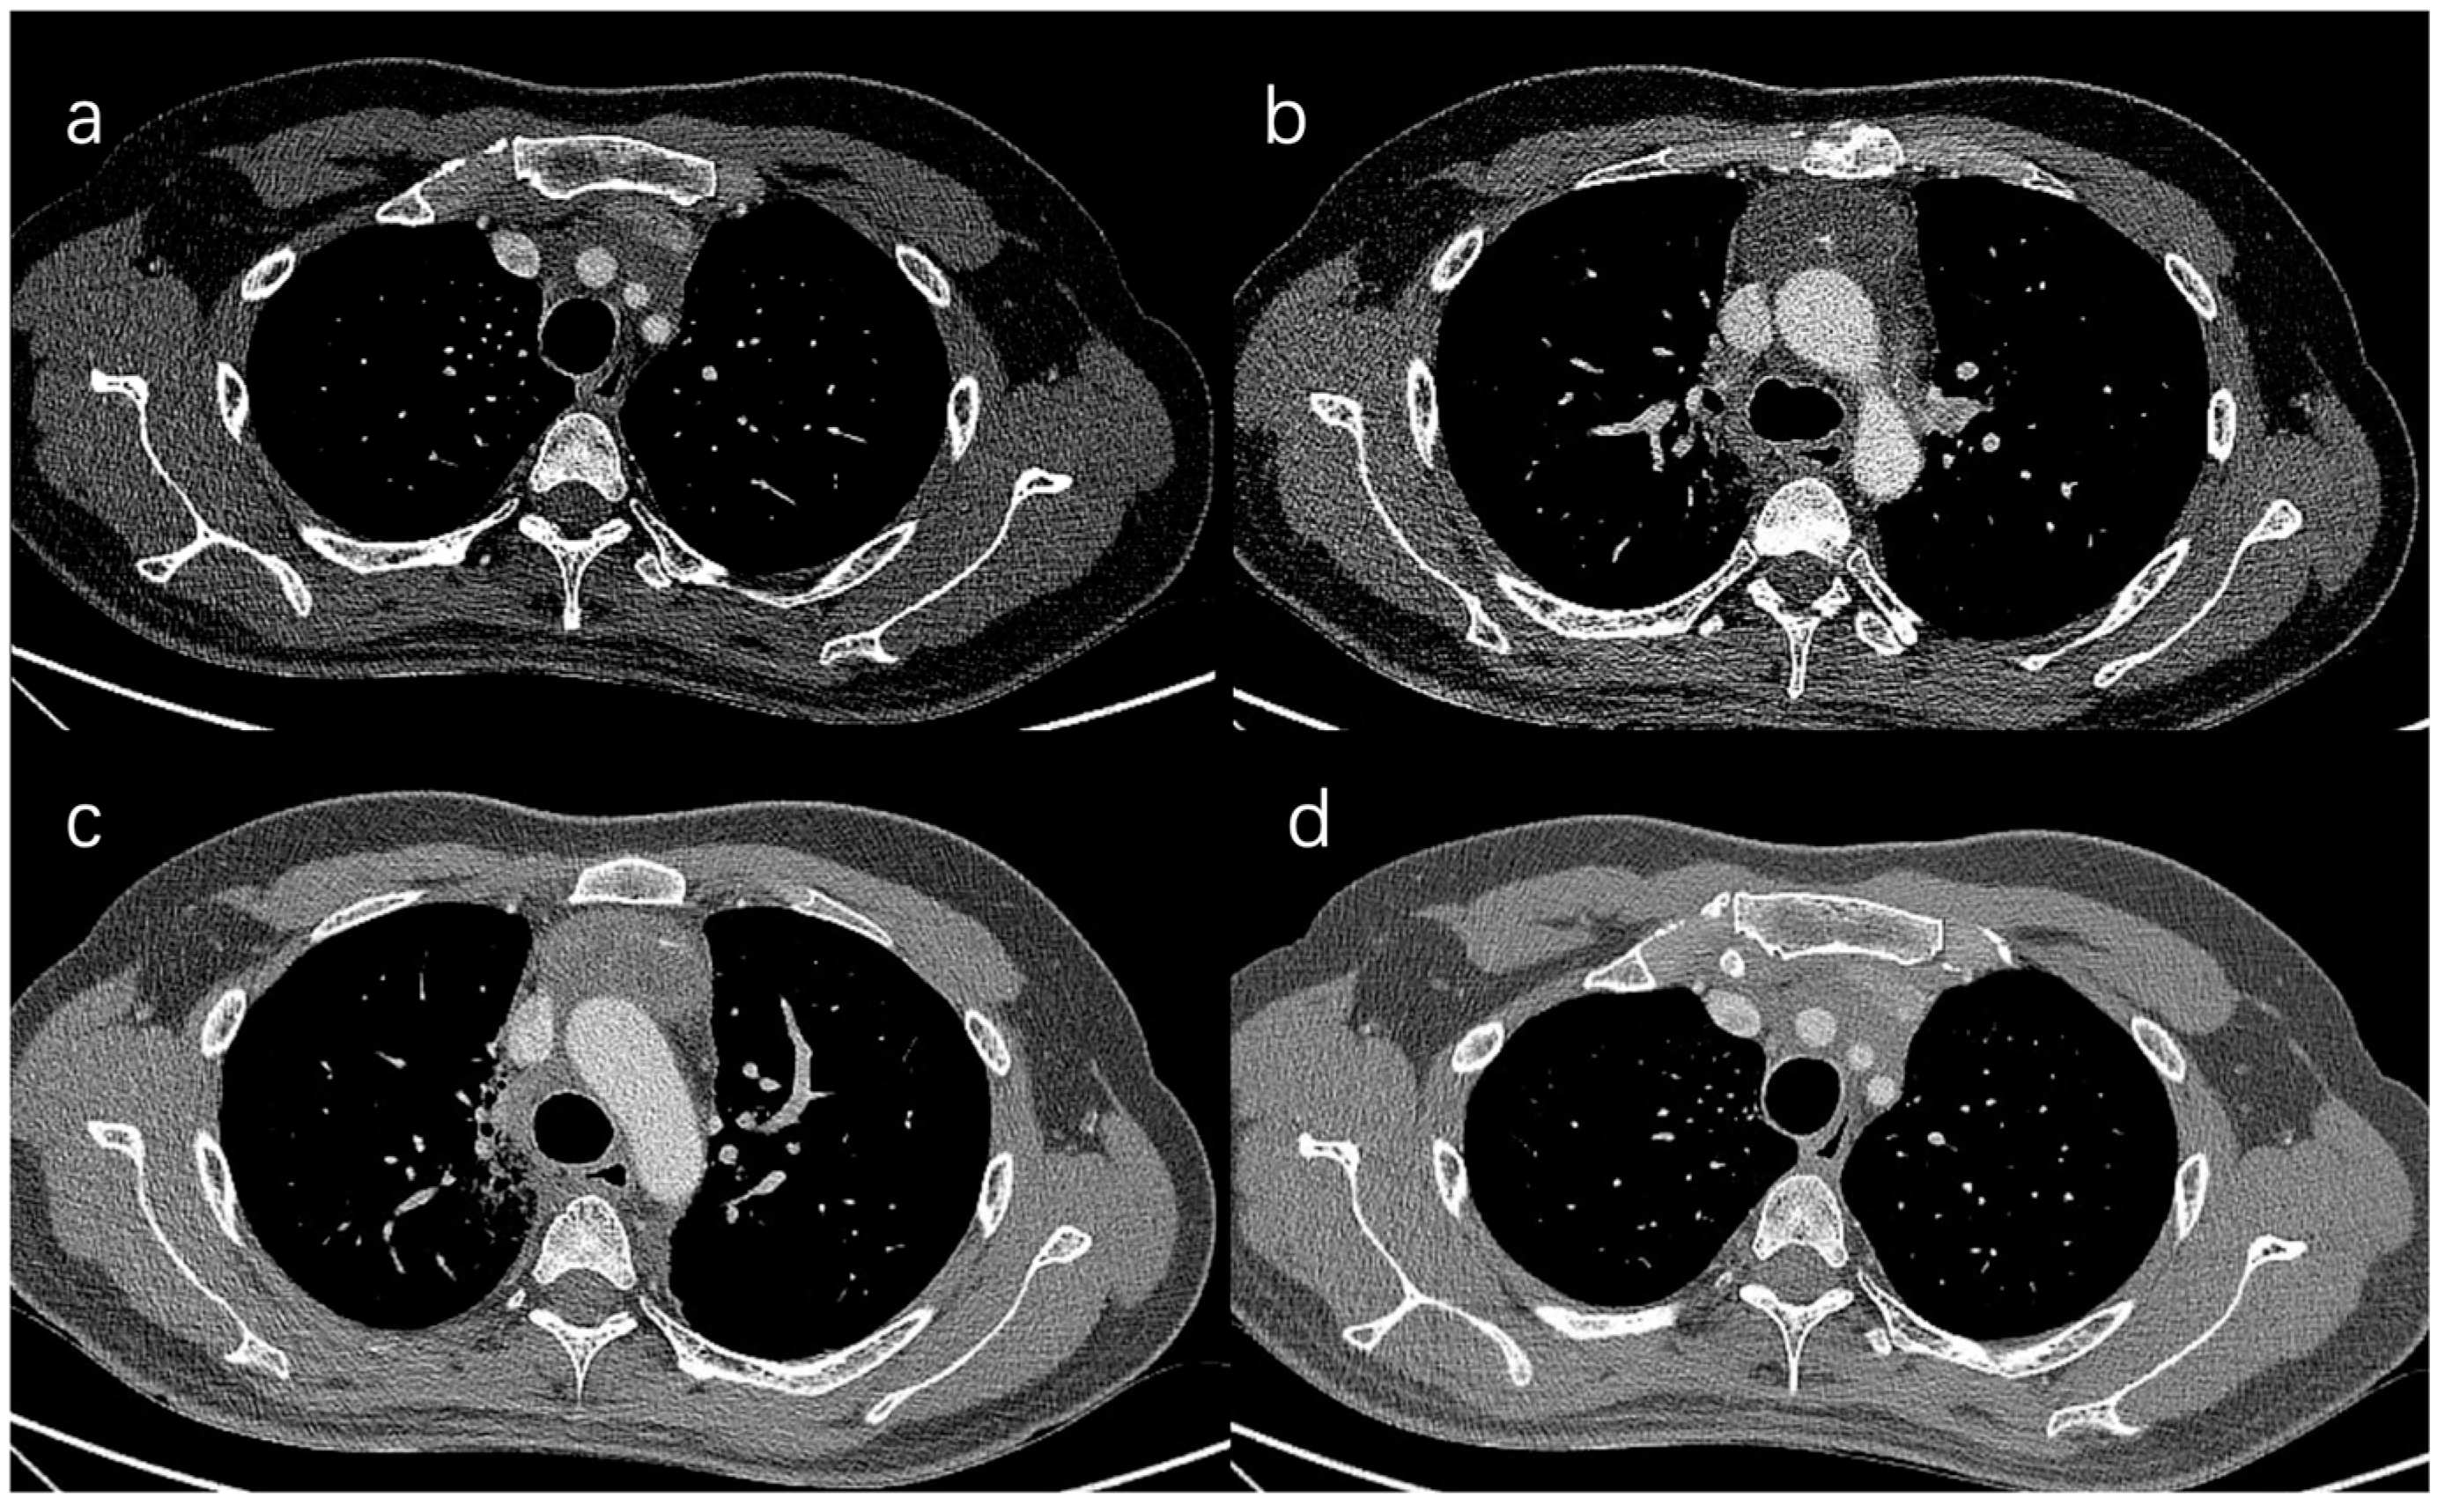

- Wang, X.; Aramini, B.; Xu, H.; Fan, J. Thymectomy with angioplasty through a thoracoscopic subxiphoid approach with double elevation of the sternum in Masaoka stage III thymoma. JTCVS Tech. 2021, 8, 208–210. [Google Scholar] [CrossRef]

- Jiang, J.H.; Gao, J.; Zhang, Y.; Wang, H.; Tan, L.J.; Ding, J.Y. Modified Subxiphoid Thoracoscopic Thymectomy for Locally Invasive Thymoma. Ann. Thorac. Surg. 2021, 112, 1095–1100. [Google Scholar] [CrossRef]